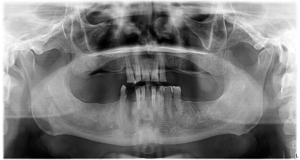

În Martie 2023, Domnul G. a ajuns în clinica noastră având dantura afectată și dorind o reabilitare totală cu ajutorul procedurii „Dantură fixă pe implanturi dentare”.

În timpul intervenției, i-au fost inserate 6 implanturi în mandibulă și 6 în maxilar, pentru a susține o dantură completă de care se bucură în prezent.